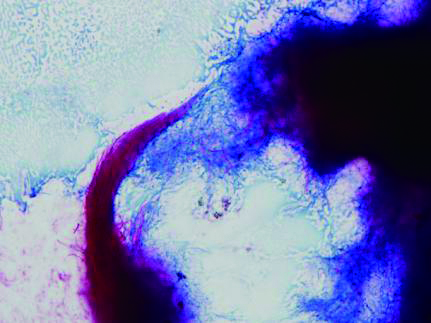

| 图 3 胸水标本表现出分歧杆菌革兰染色阳性提示奴卡菌感染(1 000×) |

| 图 4 抗酸染色见不典型分歧杆菌 |